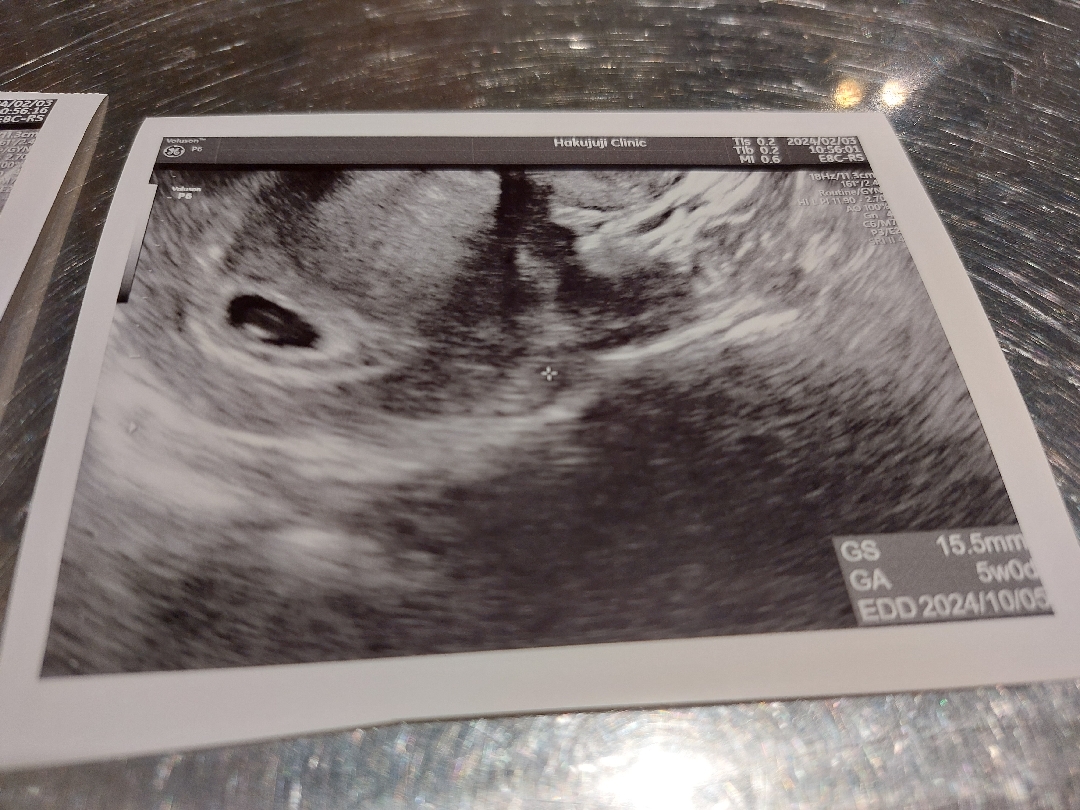

사진이 좀 흐릿해서 죄송해요ㅠㅠ 네이버 주수로는 7주0일차인데, 병원에서는 5주 중반쯤이라는 말을 들었어요. 애기집 15.5미리구요.. 다른 분들은 병원에서 이런저런 이야기 들으시던데, 여기 쌤이 애기집 위치라던가 피고임이라던가 난황이라던가 그런 설명을 전혀 안해주셔서 불안하기만 하네요ㅠㅠ 1주일 전에 갔을 때는 9.1이었던거 생각하면 애기집은 잘 크고 있는 것 같은데, 난황 크기 어때 보이시나요..? 흐릿해서 잘 안 보이기는 한데 은근히 커 보이기도 해서 걱정이에요.... 친정엄마는 왜 그리 병원 자주 가냐며 2주 정도 내비두라는데, 애기 심장소리도 못 들어서 하루빨리 또 가고싶어요ㅠㅠ(심장소리 12주나 돼야 듣는다고 선생님이 그러던데..이게 맞는건가요...;;다른분들 5주차도 들으시던데..) 병원은 어차피 집에서 거리도 있어서, 한 번만 더 가서 추천장 받고 이동하려구요..

심장소리 7주차에 대부분 들을 수 있어요, 5주 아기집 6주 난황 7주 심장소리.. 네이버주수는 생리주기 28일 훌쩍 넘어가면 의미 없어요.

저도 5주차때 다이아반지만 확인했어요! 너무걱정마세요 아가집도 동글하고 좋은데요!! 다른말씀안하시면 너무신경안쓰셔도 될꺼같아요 엄마가 마음편하게있어야 아가도 건강하죠!! 아마 다음주쯤에는 심소 들으실수있을꺼같아요 다이아반지때는 저도 안들었어요 ㅎㅎ 검진때 궁금하신건 물어보세요! 피고임같은건없는지!! 지금상태로는 아무탈없이 잘크고있어보여용!! 저는지금 7주차인데 2주내내 갈색냉나와요 !!그래도 아무탈없이 아가잘크고있답니다!! 걱정마시구맘편히가지셔요❤️